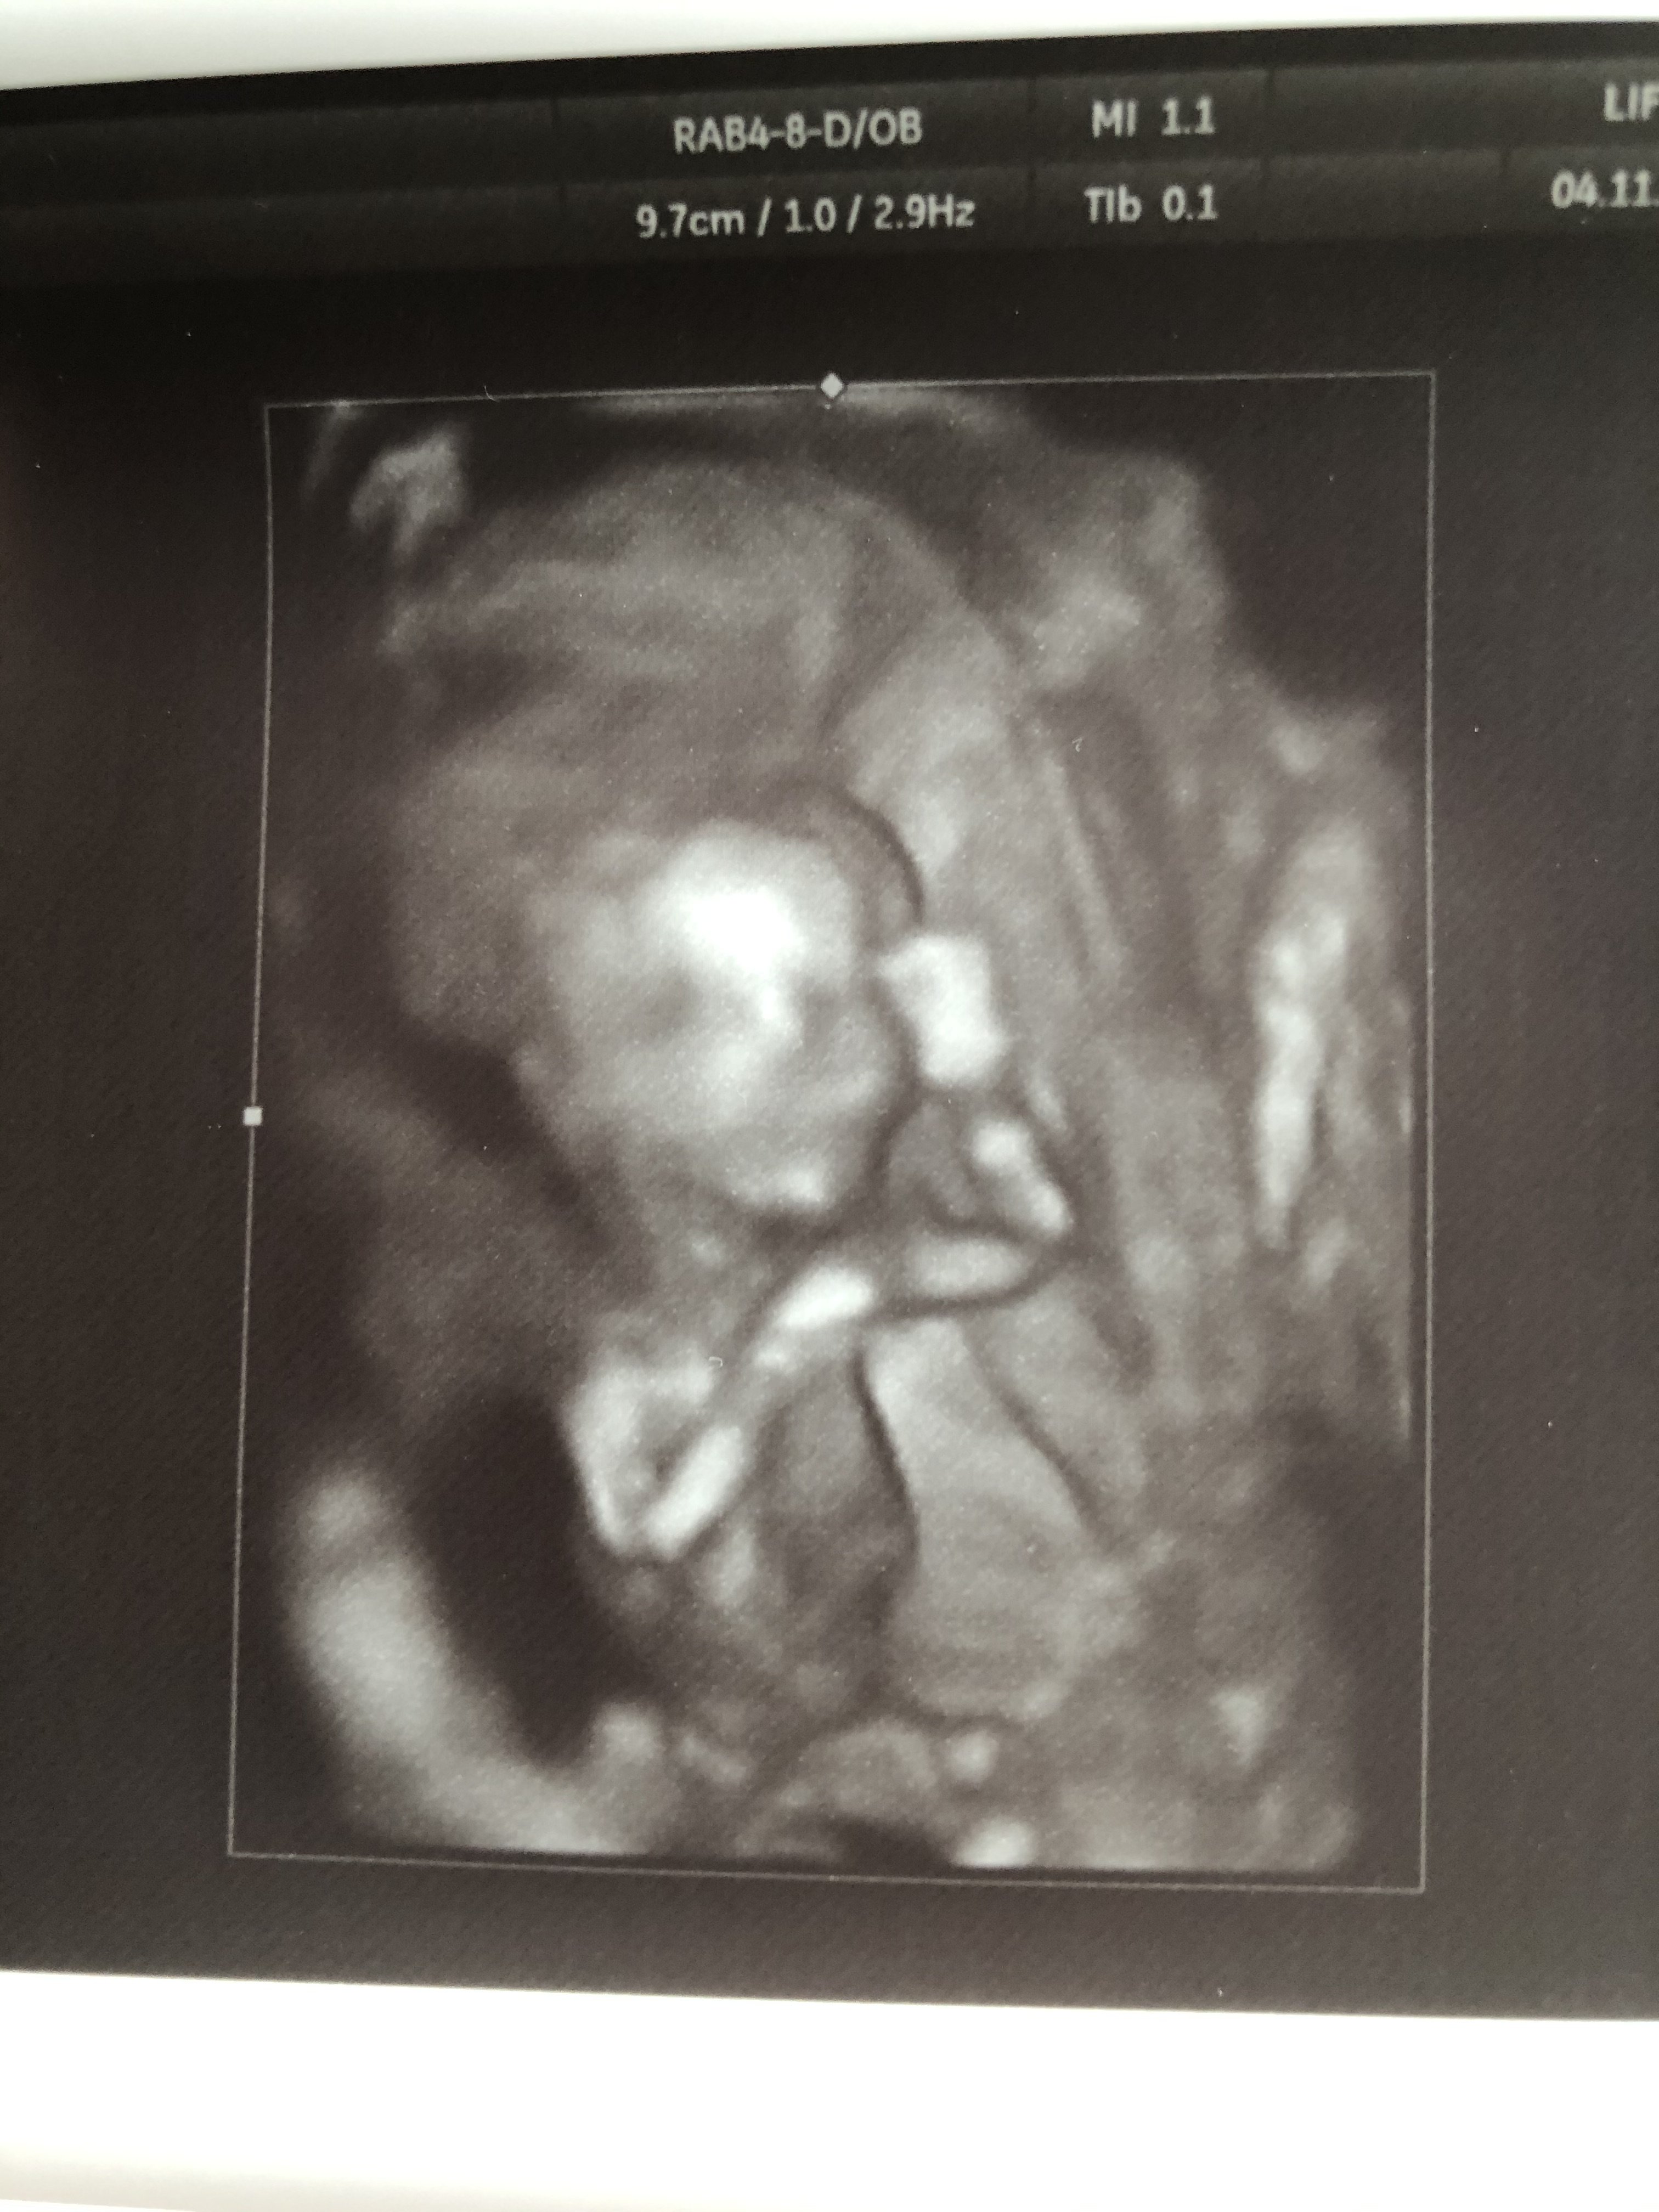

Mój syn tez wczoraj patrząc na USG stwierdził ze to dziewczynka ale mi sie wydaje ze to dlatego ze bardzo chce siostrę. Mąż widział siusiaka a to noga była [emoji23][emoji23][emoji23] ale jemu sie marzy drugi syn.Moja córka (7lat w grudniu) od początku twierdziła ze mam w brzuchu siostrę i jak wczoraj jej powiedzieliśmy ze miała racje i pokazaliśmy zdjęcie - to skomentowała to zdaniem „to jakieś kości, ale widać ze dziewczynka bo ma długie włosy i zaczesane na bok”Zobacz załącznik 1041628